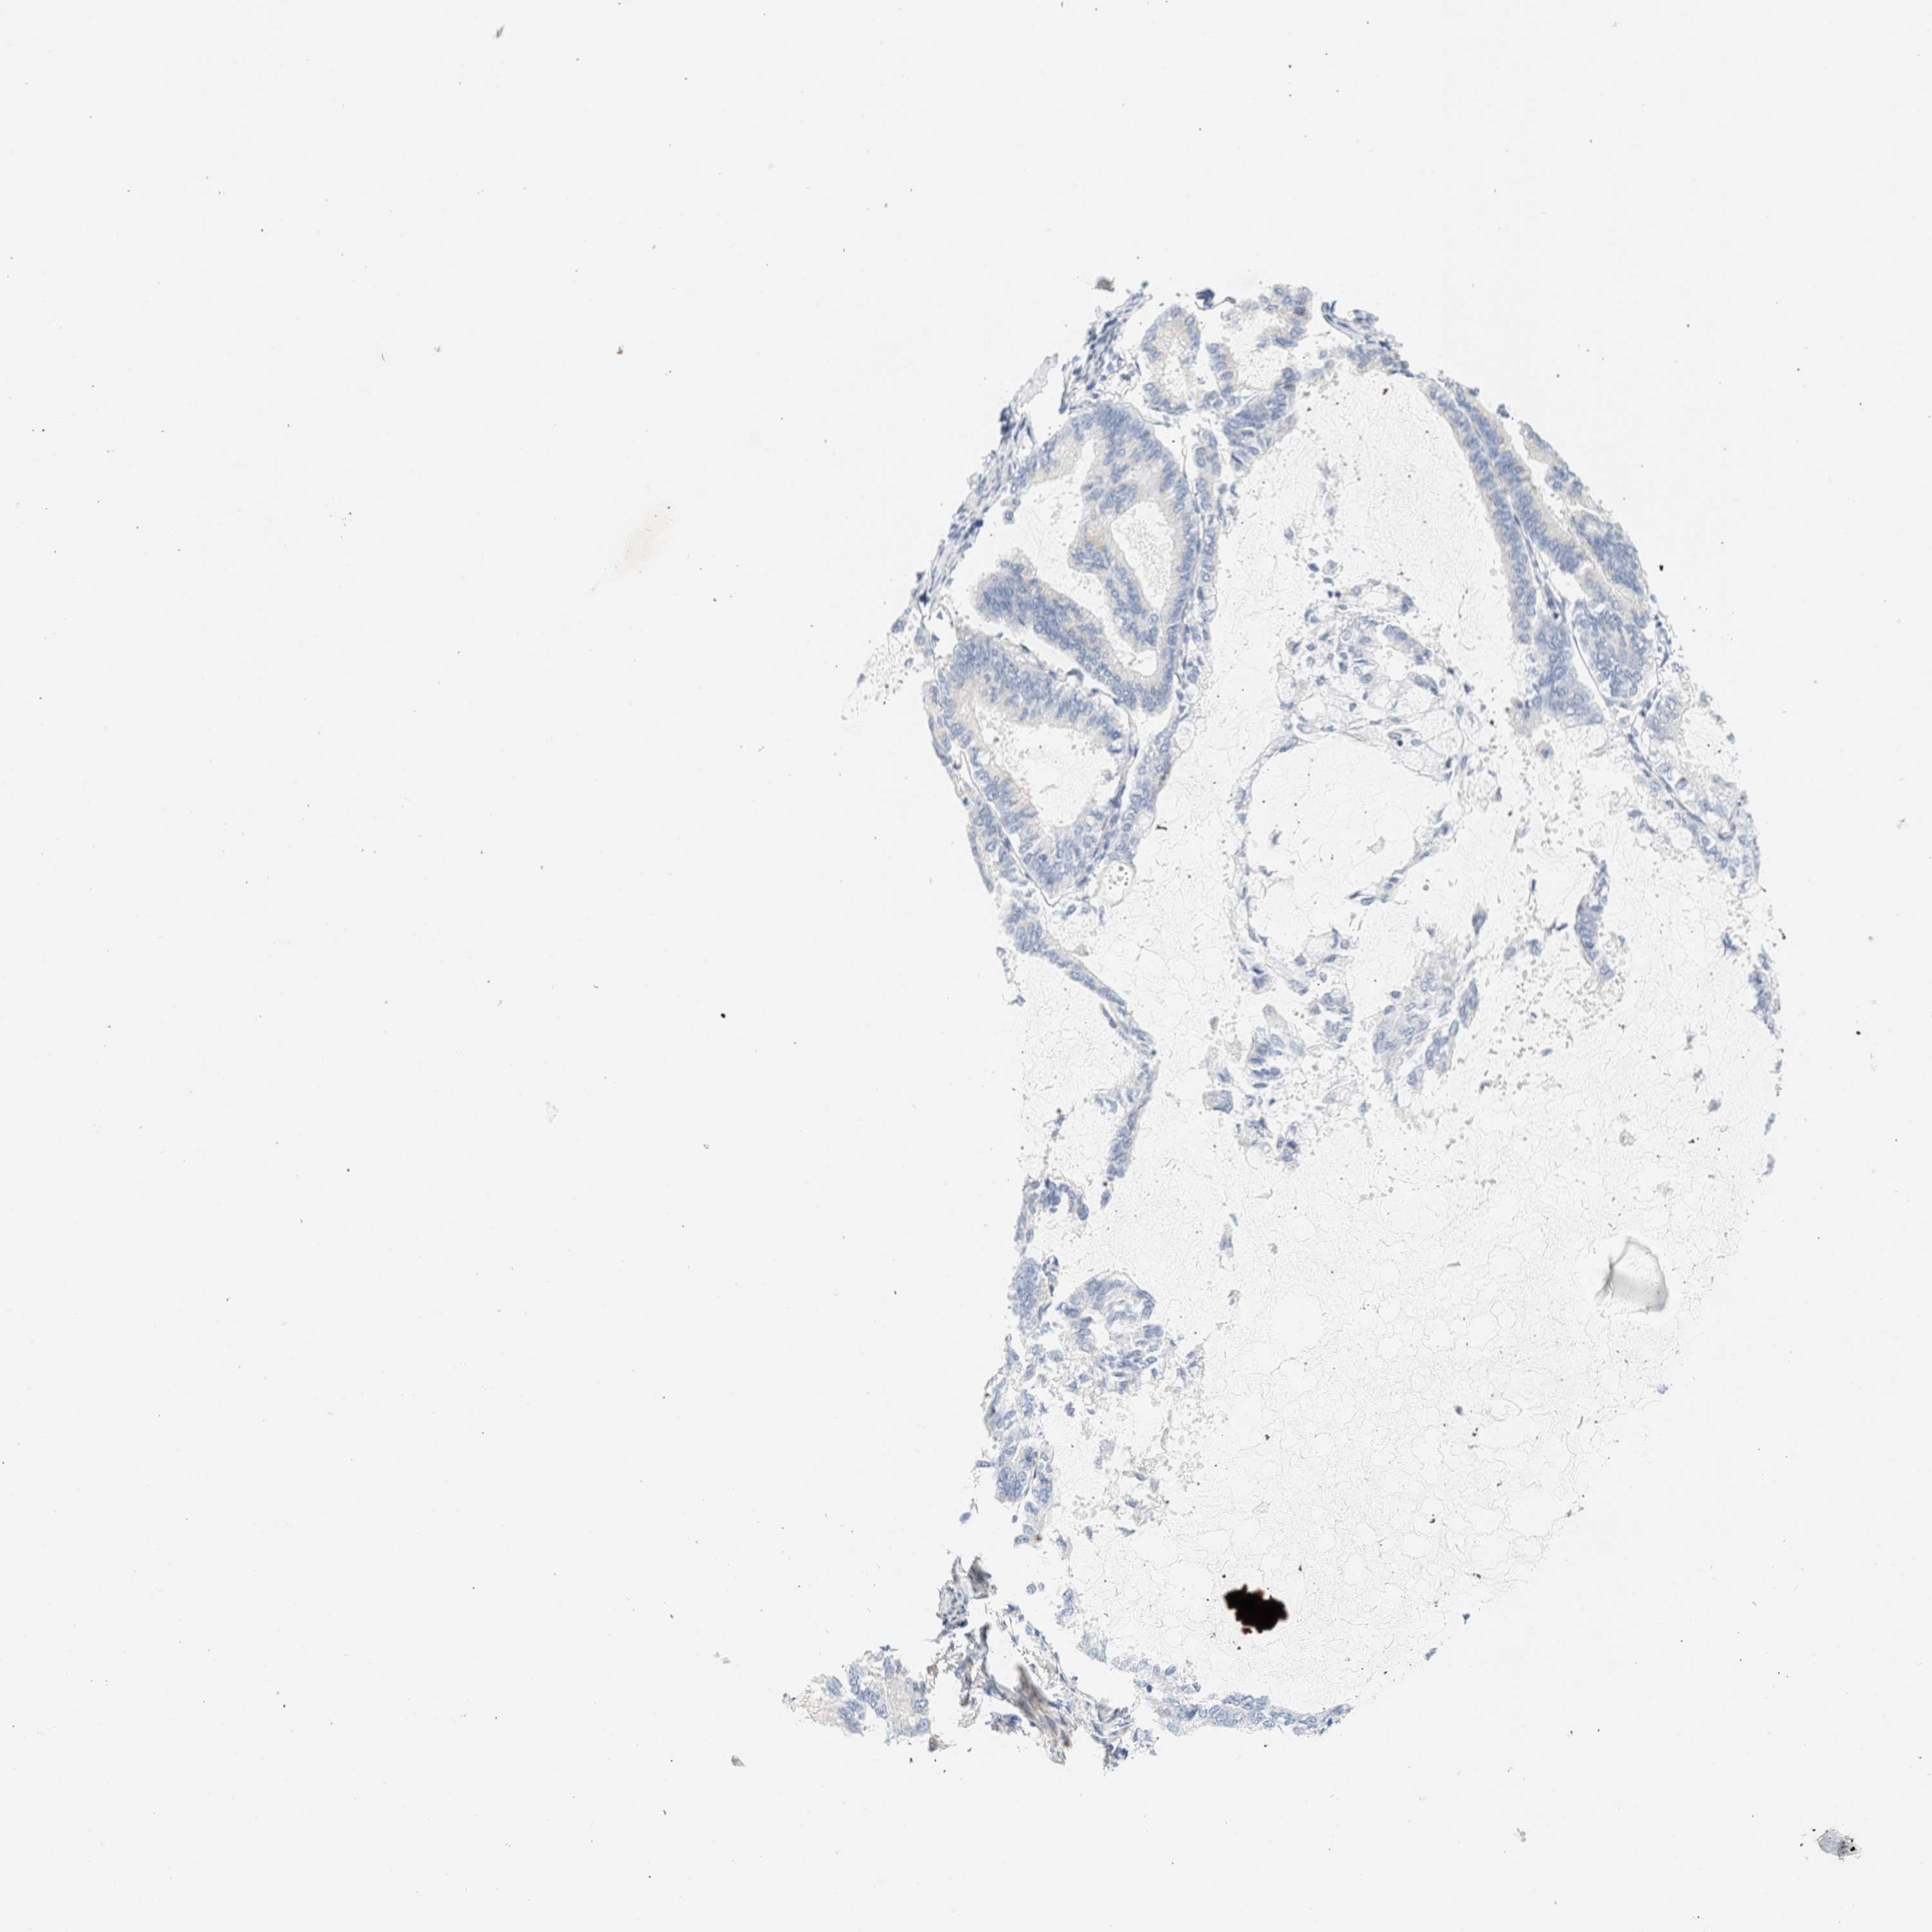

ENDOMETRIAL CANCER - Protein expressioni

A mouse-over function shows sample information and annotation data. Click on an image to view it in a full screen mode. Samples can be filtered based on level of antibody staining by selecting one or several of the following categories: high, medium, low and not detected. The assay and annotation is described here.

Note that samples used for immunohistochemistry by the Human Protein Atlas do not correspond to samples in the TCGA dataset.

Antibody stainingi

Antibody staining in the annotated cell types in the current human tissue is reported as not detected, low, medium, or high, based on conventional immunohistochemistry profiling in selected tissues. This score is based on the combination of the staining intensity and fraction of stained cells.

Each image is clickable and will lead to virtual microscopy that enables deeper exploration of all samples and also displays staining intensity scores, fraction scores and subcellular localization as well as patient and tissue information for each sample.

Antibody HPA018034

Staining

High

Medium

Low

Not detected

Intensity

Strong

Moderate

Weak

Negative

Quantity

>75%

75%-25%

<25%

None

Location

Nuclear

Cytoplasmic/membranous

Cytoplasmic/membranous,nuclear

Adenocarcinoma, NOS